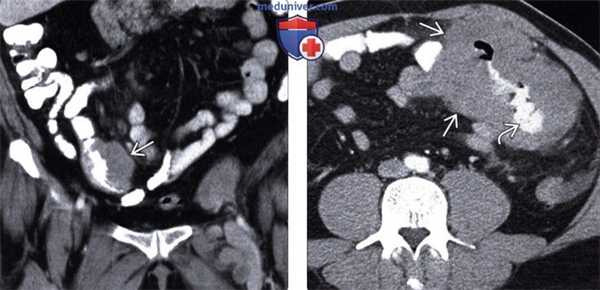

(Слева) При КТ с контрастным усилением в корональной плоскости визуализируется опухолевидное утолщение мягких тканей по краю подвздошной кишки. Обратите внимание на отсутствие обструкции кишки несмотря на значительное опухолевое поражение. Это характерное проявление лимфомы.

(Справа) На аксиальной КТ с контрастным усилением у ВИЧ-инфицированного пациента выявлено большое изъязвленное образование с наличием контраста в просвете тонкой кишки. Обратите внимание на типичное аневризматическое расширение просвета пораженной кишки вследствие опухолевой инфильтрации. Это часто встречающееся проявление лимфомы кишечника.

• ЖКТ: изменения похожи на таковые при НХЛ, включая опухолевидное утолщение кишечной стенки, аневризматическое расширение, изъязвленное полиплоидное объемное образование, или подслизистые узлы

о Изменения аналогичны таковым при НХЛ у пациентов с нормальным иммунным статусом:

- Опухолевидное утолщение стенки кишки (наиболее часто) с аневризматическим расширением просвета

- Доминирующее полиплоидное образование (часто с изъязвлением) или множественные подслизистые узлы

- Может проявляться инвагинацией

о В отличие от лимфомы в общей популяции, при данном заболевании в значительной степени превалирует язвообразование и перфорация стенки кишки:

- Спонтанная перфорация может быть первым симптомом ПТЛЗ